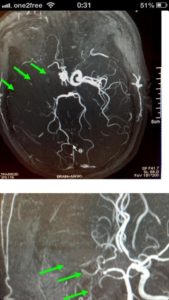

罗先生被送往私家医院的第一步是进行紧急磁力共振造影,报告显示罗先生右边颈和脑部血管大动脉全部都被血栓堵塞着,右边大脑缺血水肿,导致左边手脚冇力和神智半昏迷。经过脑血管外科医生的诊断和急救,在全身麻醉下,医生使用尤如髪丝微细的导管,经过病人右边大腿的腹股沟的大动脉而入,导管再经过腹部和胸腔的大动脉一直向上,游走到病人右边的颈和脑部血管大动脉,进行机械式血栓吸取内血管治疗急救。

经过1小时的血管急救,所有血栓都被移除,罗先生的右颈和脑部血管都给顺利打通,脑部缺血情况立即得到改善。血栓被吸取后, 脑血管外科医生发现罗先生的右颈内动脉有严重血管狭窄的情况,这个狭窄就是罗先生中风的主要原因。医生因此植入血管支架来重新扩张狭窄的血管,以防止罗先生将来中风复发。全身麻醉清醒后,罗先生的大脑意识和手脚活动能力即时好转,他其后再被送回另一间公立医院继续康复治疗。

| 导管游走到病人右边的颈和脑部血管大动脉,进行机械式血栓吸取 | |

| 血栓被吸取后, 右颈和脑血管都给顺利打通,脑部缺血情况立即得到改善 | |